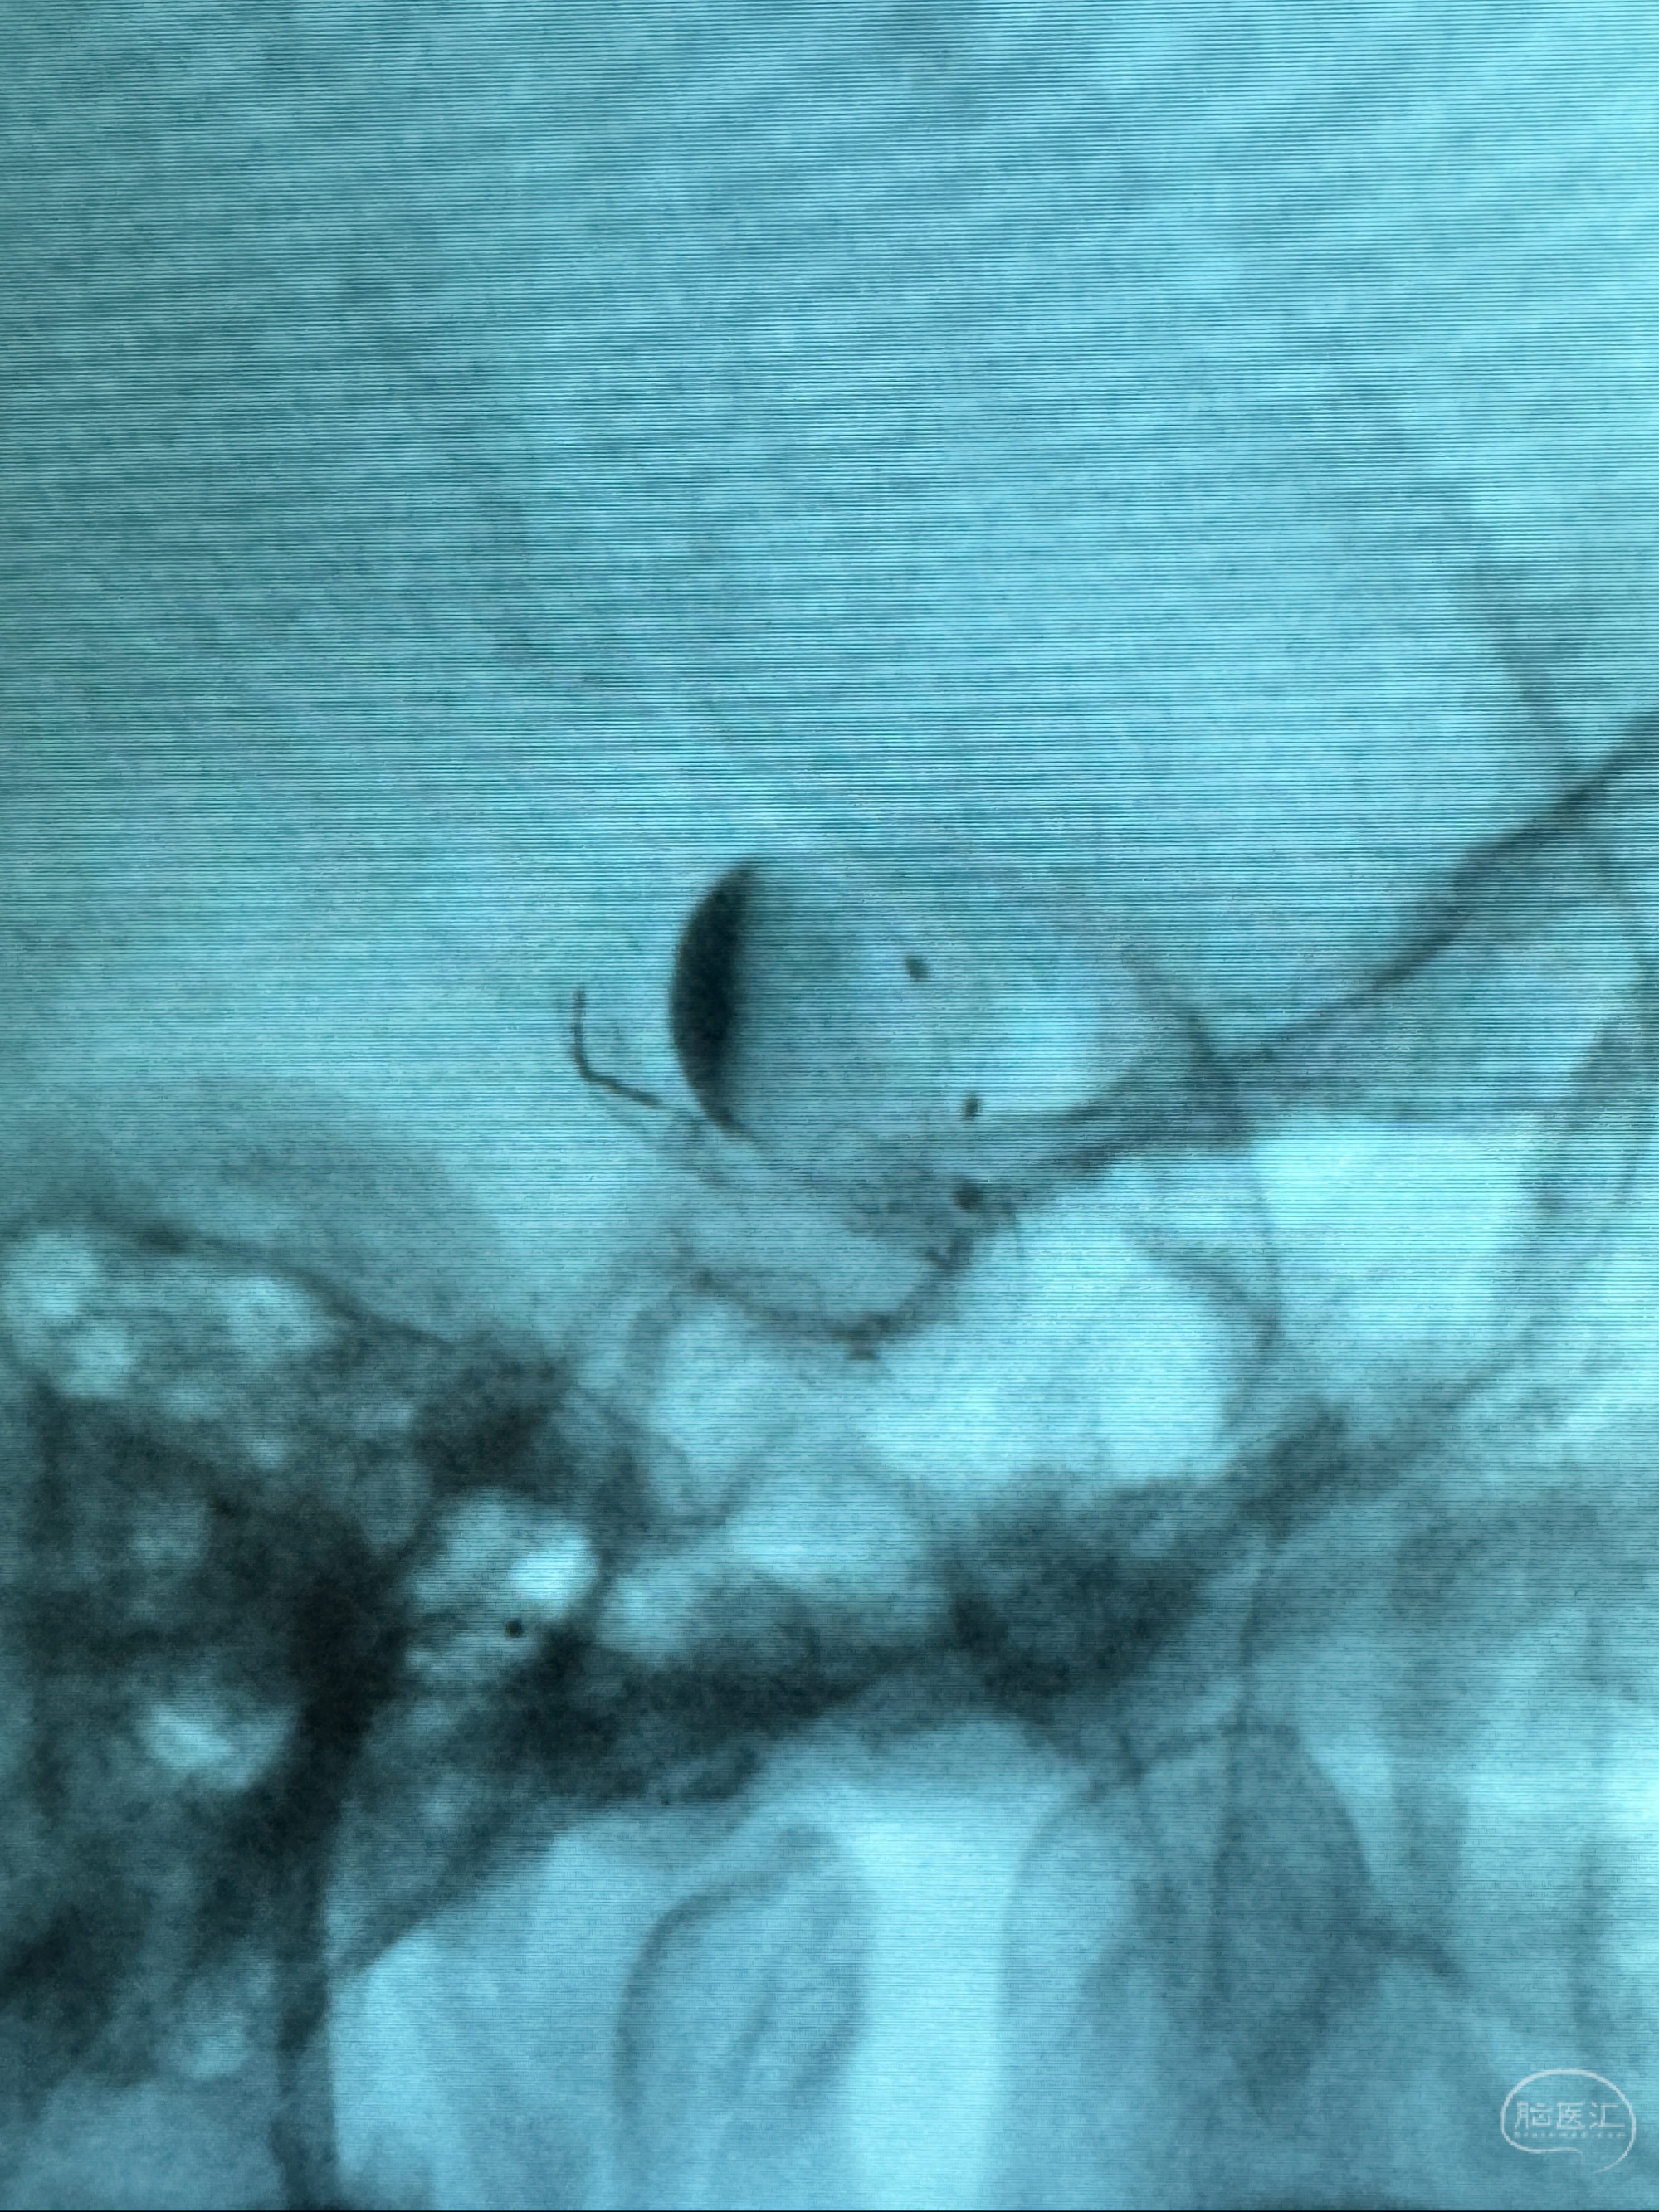

透视可见红圈部分为支架导管的头端

手推冒烟显示支架位置及展开情况,箭头为支架导管的位置

最后再看看颅内血管是否有异常

看动脉瘤内造影剂滞留,未见明确射流,遂撤出预留的栓塞微导管,快速结束手术,经导引导管灌注替罗非班250ug。